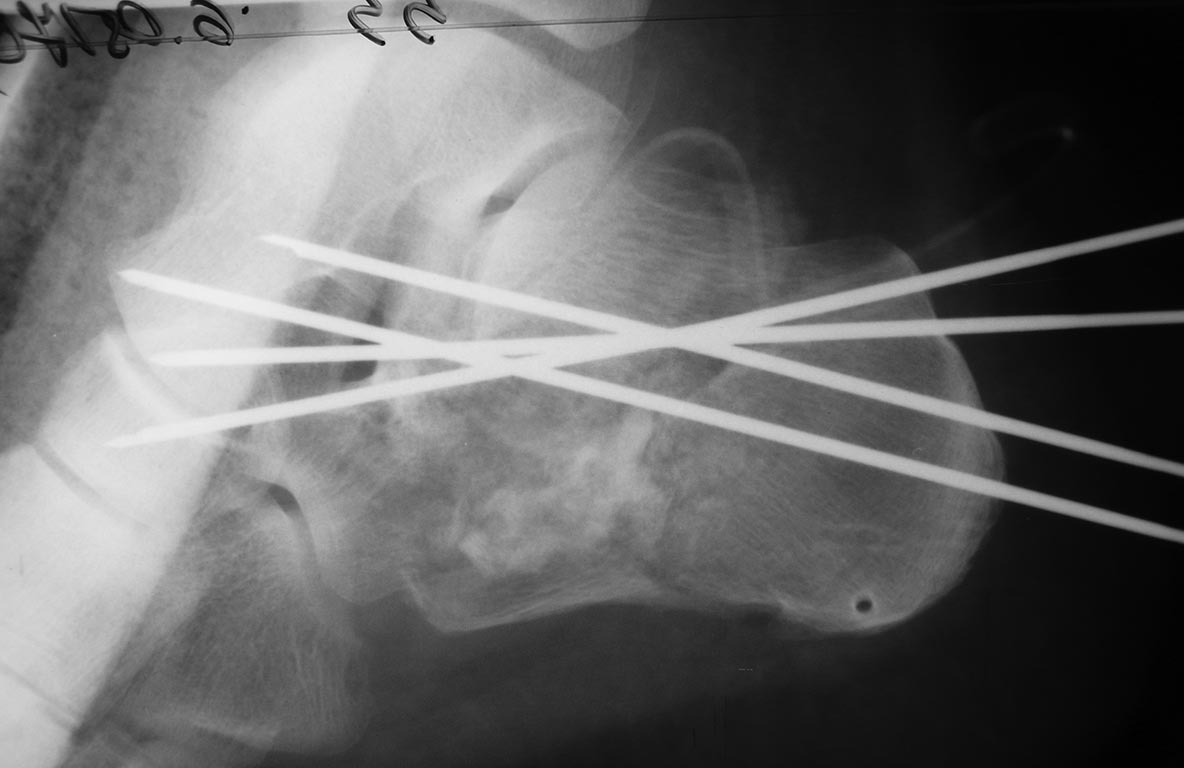

Пациента прооперировал 5 мая. Произвел аутопластику костной крошкой и

фиксацию спицами. Выкладываю снимки

Вложение не в текстовом формате было извлечено…

Имя     : P1120343.JPG

Тип     : image/jpeg

Размер  : 39498 байтов

Описание: отсутствует

Url     : http://weborto.net:8080/pipermail/ortho/attachments/20170508/016c5547/attachment-0003.jpeg